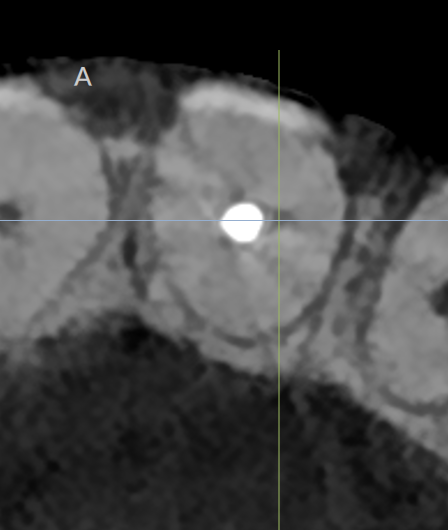

Počevši od dijagnostičkog dela, 3D snimanje je osnovni alat za kompletiranje zagonetke i pronalaženje odgovora, kao i za pripremu potpunog plana lečenja, kako za svaki jednostavan tako i za komplikovane slučajeve. Veštačka inteligencija (AI) je odličan dodatak u pogledu 3D snimanja. Već neko vreme koristim softver DTX Studio Clinic, koji ima mnoge funkcije veštačke inteligencije i poboljšane funkcije slike koje mi mnogo pomažu u svakodnevnoj praksi. Kada se kombinuje sa pravilnom rezolucijom i vidnim poljem za endodonciju, postaje veoma moćan dijagnostički alat. Nedavno smo nadogradili našu i-CAT jedinicu na DEXIS OP 3D jedinicu, koja ima mnogo prednosti u pogledu vidnog polja i kvaliteta slike, a savršena je kada se kombinuje sa DTX softverom. Digitalna 3D slika omogućava otkrivanje neuobičajene anatomije. U slučaju pacijenta koji se žalio na bol i pritisak na zub nakon što je neko vreme bio podvrgnut terapiji kanala korena, pažljivo čitanje CBCT skeniranog područja otkrilo je drugi kanal u centralnom sekutiću i omogućilo nam da lociramo furkaciju (Sl. 1–3).

Sl.2: Lokacija furkacije

Fig. 2: Location of the furcation.